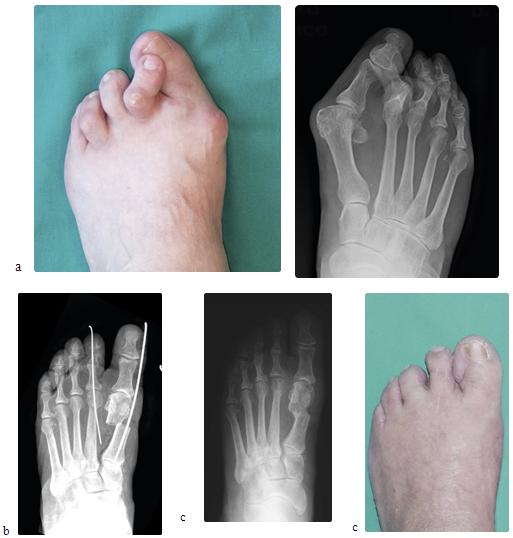

Caso 1: Alluce valgo e dita ad artiglio associati a metatarsalgia

Femmina, 70 anni, alluce valgo bilaterale di grado severo, associato a deformità ad artiglio del secondo e terzo dito (a). La deformità dell'avampiede causava metatarsalgia da sovraccarico del secondo e terzo raggio metatarsale. Sottoposta a intervento chirurgico di osteotomia del primo metatarso con tecnica SERI, osteotomia del secondo e del terzo metatarso con tecnica di Weil e correzione della deformità in griffe del secondo e terzo dito (b), con ottima correzione clinica e radiogradica della deformità (c).

Caso 4: Alluce valgo e dito ad artiglio

Femmina di 63 anni affetta da alluce valgo e deformità ad artiglio del 2° dito associata a lussazione della 2° metatarsofalangea (a). La deformità dell'avampiede era causa di metatarsalgia resistente al trattamento medico e ortesico. Sottoposta ad intervento chirurgico di osteotomia correttiva del primo metatarso con tecnica S.E.R.I., riduzione della lussazione metatarsofalangea e correzione della deformità ad artiglio del 2° dito (b), a distanza di 8 mesi dall'intervento chirurgico, l'avampiede si presenta corretto e la metatarsalgia risolta. Il controllo radiografico (c) mostra il rimodellamento del metatarso conseguente all'osteotomia.